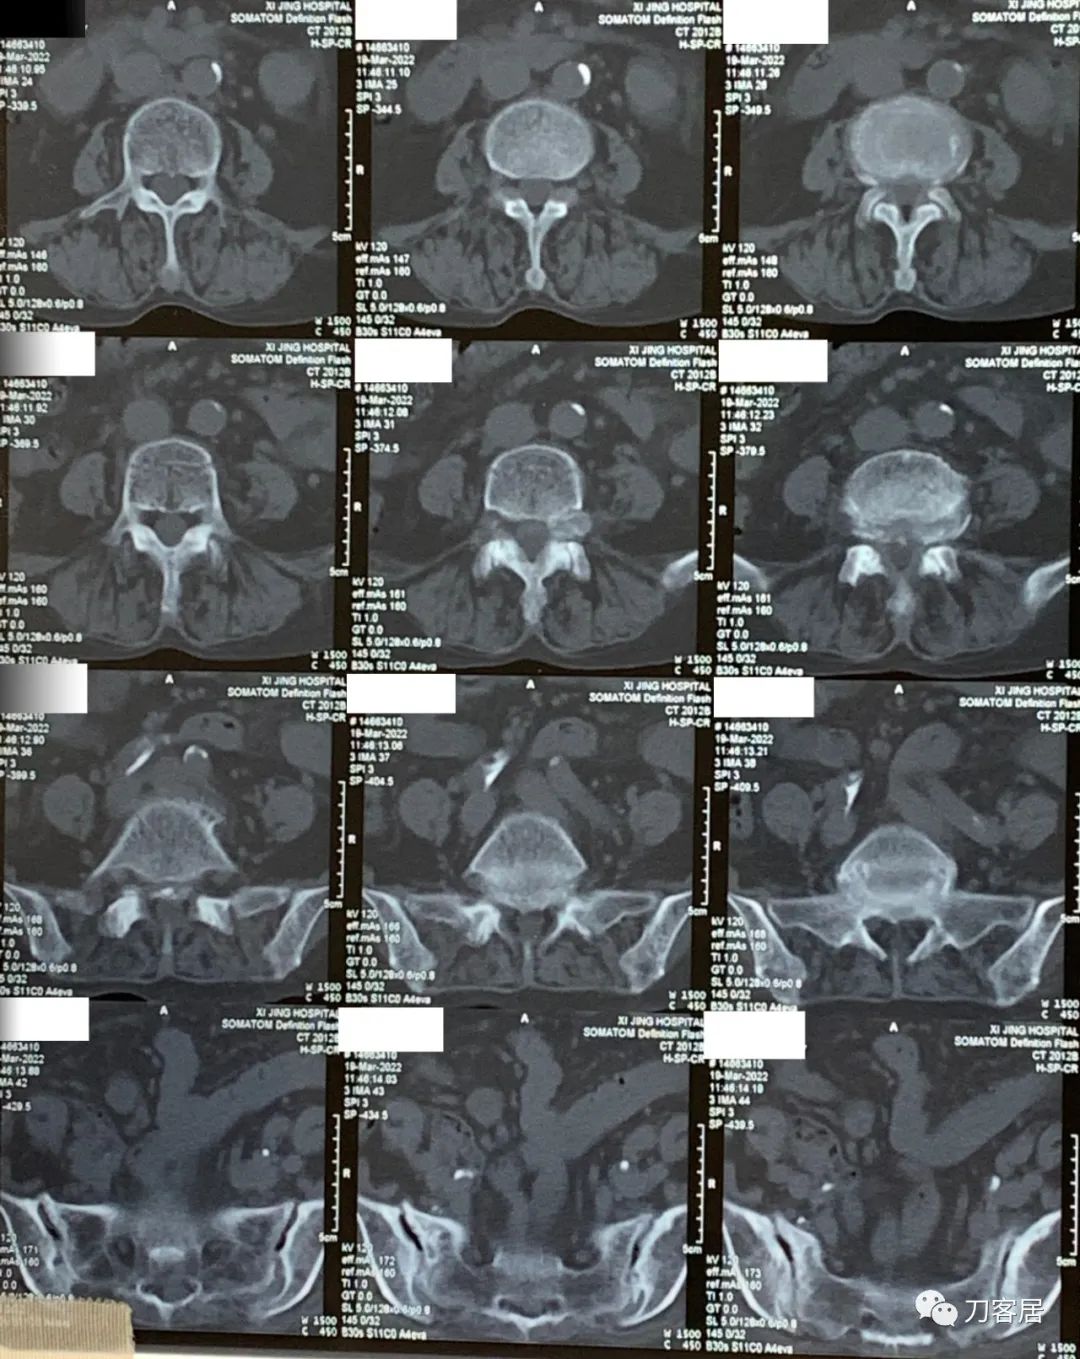

3月19日在我院神经外科门诊就诊时,做了腰椎CT平扫。腰椎CT提示腰4-5,腰5骶1椎间盘突出,腰4-骶1椎管狭窄。

图1. 20220319西京医院腰椎CT01

图2. 20220319西京医院腰椎CT02

图3. 20220319西京医院腰椎CT03

图4. 20220319西京医院腰椎CT04